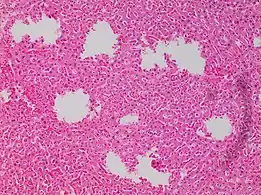

In microscopy

In microscopy, an artifact is an apparent structural detail that is caused by the processing of the specimen and is thus not a legitimate feature of the specimen. In light microscopy, artifacts may be produced by air bubbles trapped under the slide's cover slip.[1]

A crush artifact is an artificial elongation and distortion seen in histopathology and cytopathology studies, presumably because of iatrogenic compression of tissues. Distortion can be caused by the slightest compression of tissue and can provide difficulties in diagnosis.[2][3] It may cause chromatin to be squeezed out of nuclei.[4] Inflammatory and tumor cells are most susceptible to crush artifacts.[4]